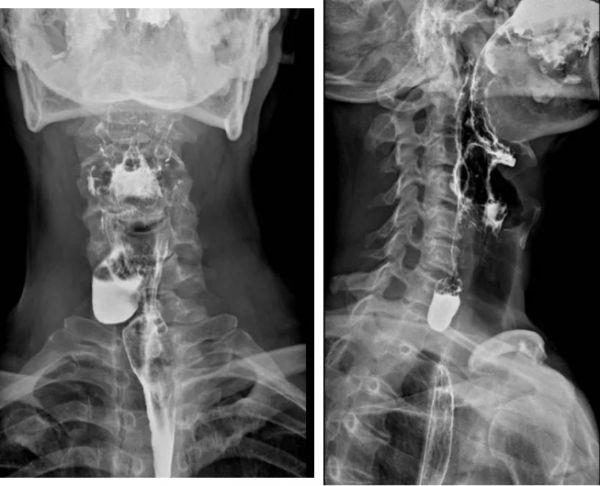

经过术前评估,李晓沛主任为赵先生开展了内镜下治疗。术中,在内镜下见憩室位于距门齿16cm处,开口1cm,吞咽时食物就会通过开口进入囊腔,导致吞咽困难。通过内镜,李晓沛主任在食管粘膜下打一“隧道”,在“隧道”内切开食管憩室间嵴,随着食道憩室嵴的切断,憩室消失了,原本食物会漏进去的“口袋”便消失了,食物不再停留于这个空间,从而解决了患者进食困难的问题。术后复查造影食管上段憩室消失,赵先生进食也没有出现吞咽困难,困扰赵先生的问题得到彻底解决。

术后患者检查结果